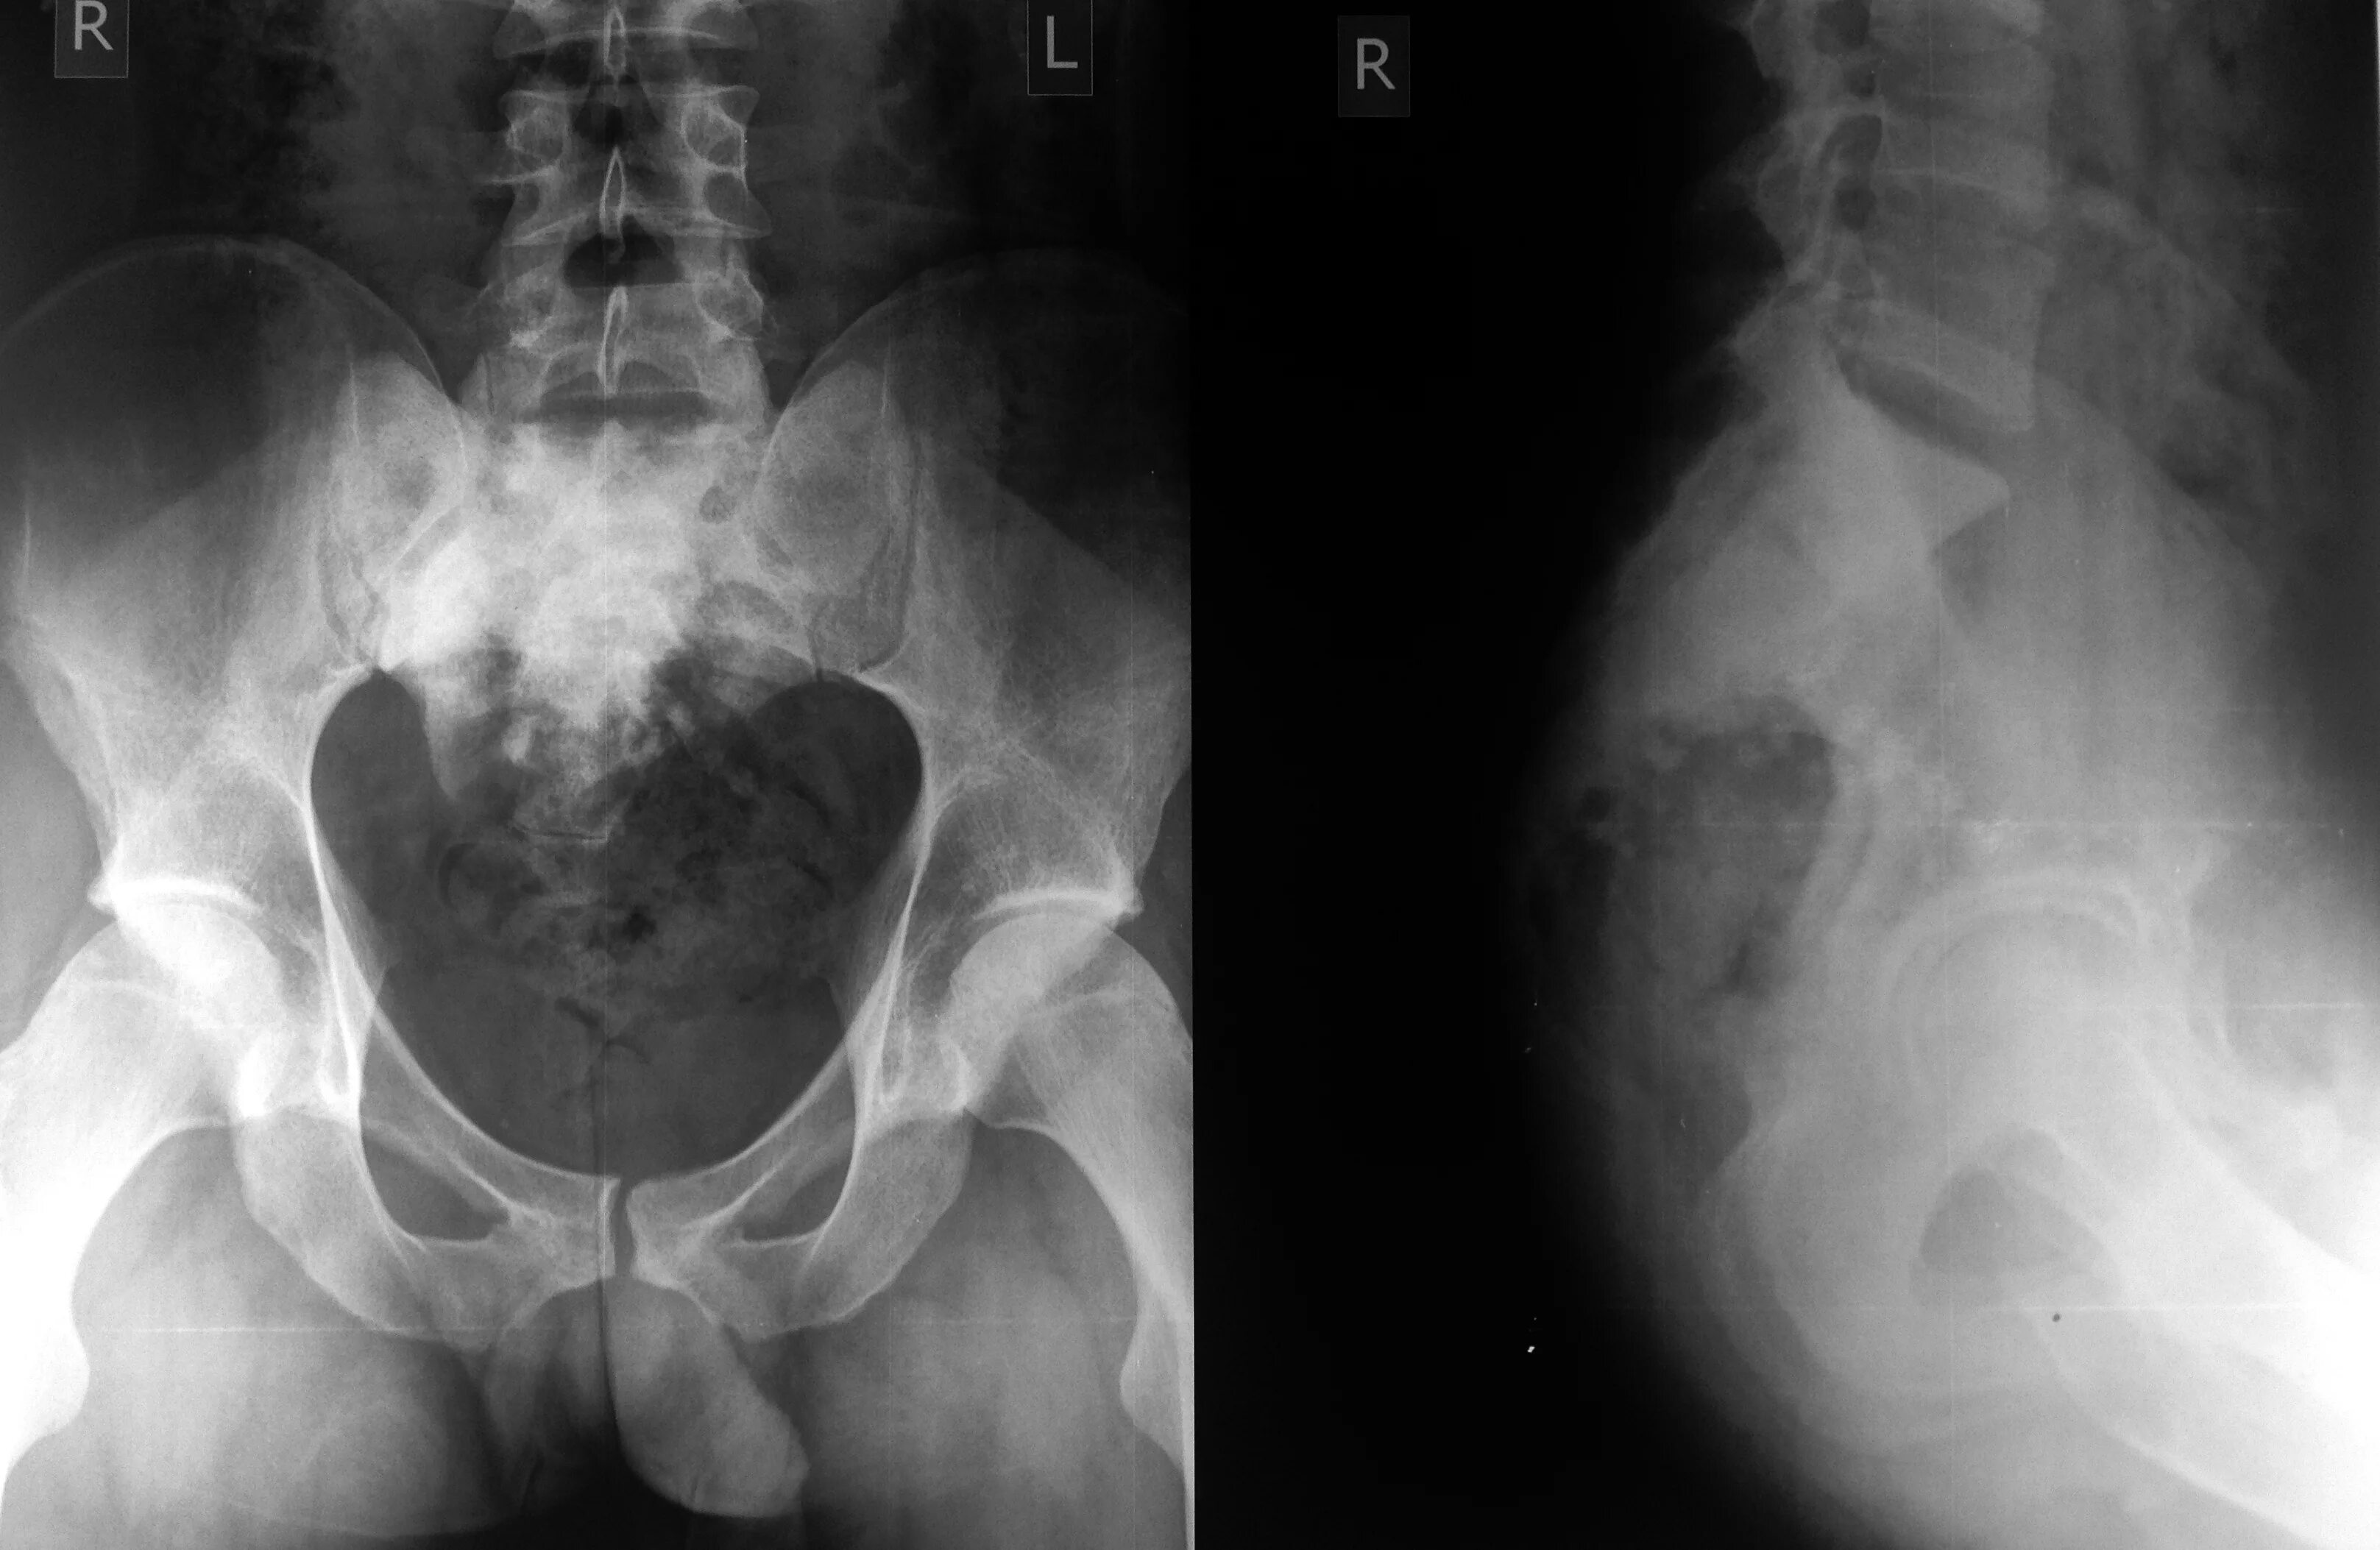

Снимок копчика